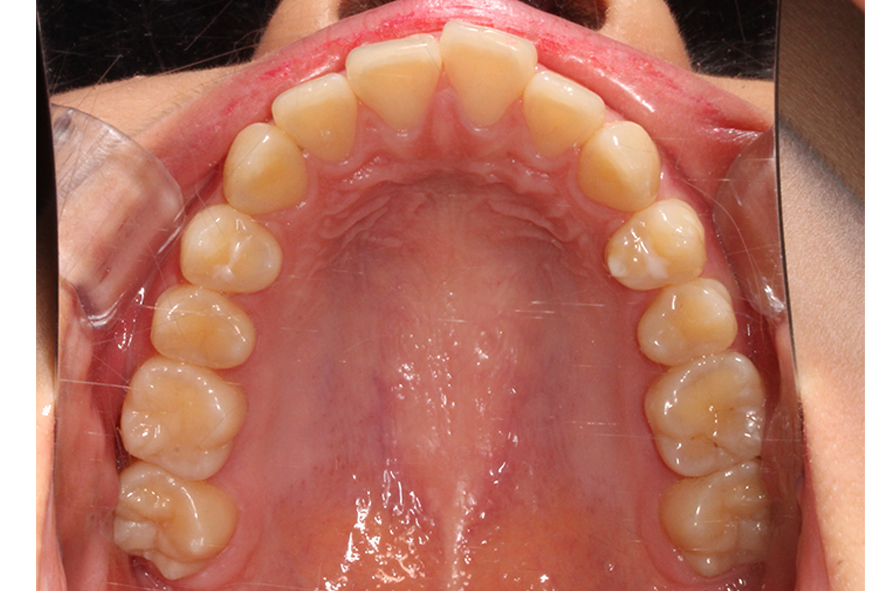

상악 교합면을 보면 전치부 치아의 각도가

순측으로 뻐드러지듯 누워있는 모습과 함께

억궁의 길이가 긴 장안모 경향을 보이는 모습인데요,

이러한 경우 하악과의 교합을 맞추기 위해

상악 치아를 발치한 후 공간을 닫아

악궁의 길이를 줄일 수 있습니다.